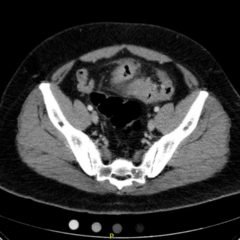

The patient had a witnessed episode of isolated left upper extremity jerking, shown in the video, during which she was completely awake and conversant. Lab results were significant for serum glucose of 1167 mg/dL, no anion gap, and negative serum/urine ketones. She had a computed tomography (CT) of the head that did not show any acute pathology, and underwent a brain magnetic resonance imaging (MRI) without any signs of stroke or other pathology, shown below.

Hyperglycemic hemichorea hemiballismus is a rare complication of hyperosmolar hyperglycemic non-ketotic syndrome (HHNS) and encompasses a range of non-patterned, involuntary movements on one side of the body.1 The pathophysiology is not fully understood, but one hypothesis suggests an increased inhibition of the subthalamic nucleus and reduction in GABA-ergic inhibition in the thalamus.2 The characteristic lesions seen on radiology include hyperdensities of the putamen, head of the caudate, and globus pallidus on CT and T1-weighted MRI contralateral to the side with symptoms, but these findings are not always seen (as in this case), nor are they specific for this disease process.3 The differential for these type of lesions also includes subacute hemorrhage, calcifications, and metal deposition.4 Most cases are benign and resolve with one to two days of normoglycemia; however, some patients can have persistent symptoms for months.2 Review of previous case reports revealed that this dyskinesia occurred more often among elderly diabetic patients but could also be an initial presentation of diabetes.5